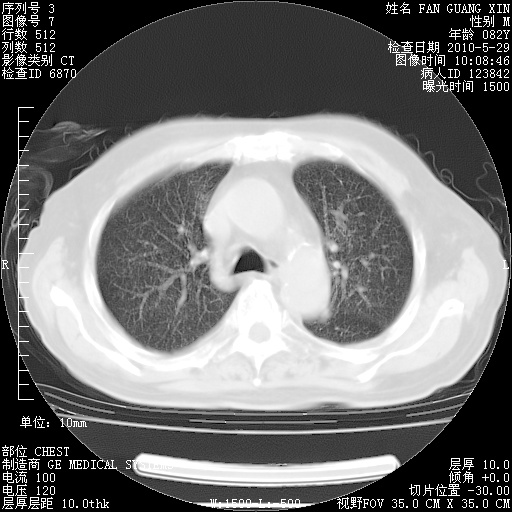

还需要哪些辅助检查?我们医院排除真菌感染没有任何检验方法,胸片好像能够排除肺部真菌感染。

补充:ENA化验全部阴性。免疫五项(IgG、IgA、IgM、C3、C4)只有C4略高。

CD3+ T细胞/淋巴细胞 46% (参考值50.00~84.00%)

CD3+CD4+ T细胞/淋巴细胞 21% (参考值27.00~51.00%)

CD3+CD8+ T细胞/淋巴细胞 25% (参考值15.00~44.00%)

CD3+CD4+ T细胞/CD3+CD8+ T细胞 0.84 (参考值0.71~2.78)

T细胞亚群是治疗5天采血。